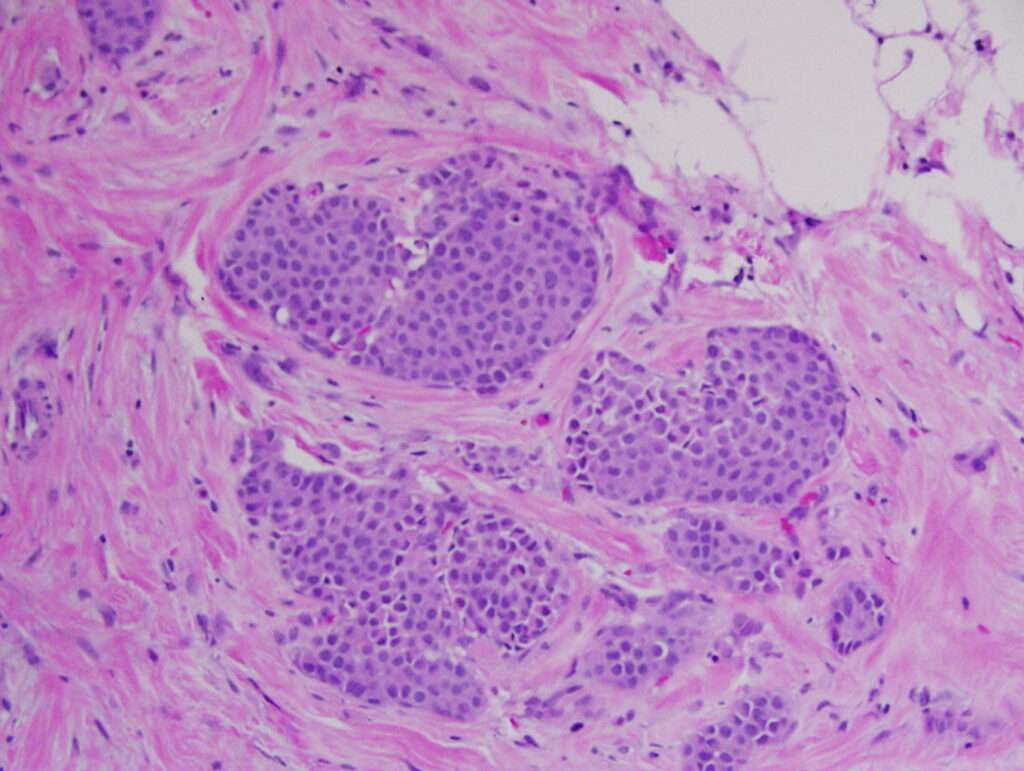

Cáncer de mama invasivo: Uno de los subtipos más comunes es el carcinoma ductal infiltrante, que constituye entre el 80 y el 90 % de los casos de cáncer de mama invasivo. Este tipo de tumor se origina en los conductos mamarios, pero a diferencia de los cánceres no invasivos, tiene la capacidad de invadir el tejido mamario circundante y diseminarse a otras partes del cuerpo. Su diagnóstico se basa en la presencia de células malignas que han atravesado la membrana basal del conducto mamario y han invadido el estroma mamario.

El carcinoma lobulillar invasivo representa otro subtipo común, constituyendo entre el 6 y el 8 % de los casos. Este tipo de cáncer se origina en los lobulillos, las glándulas productoras de leche. A diferencia del carcinoma ductal, el carcinoma lobulillar tiene una tendencia más difusa en su patrón de crecimiento y es más difícil de detectar mediante mamografía.

Cánceres no invasivos: En los cánceres no invasivos, el tumor se limita al área donde se originó y no ha invadido el tejido circundante. Un ejemplo es el carcinoma ductal in situ, que se refiere a la proliferación de células malignas dentro de los conductos mamarios sin haber invadido los tejidos cercanos. Este tipo se detecta frecuentemente en mamografías y, aunque no tiene la capacidad de hacer metástasis, puede evolucionar a un cáncer invasivo si no se trata adecuadamente.